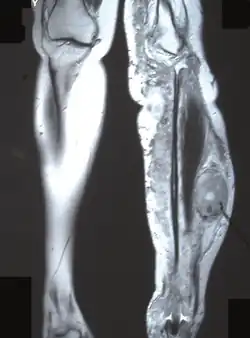

Нейрофибромы

Для данного заболевания характерно появление большого количества нейрофибром, как кожных, так и плексиформных. Кожные нейрофибромы представлены небольшими доброкачественными и ограниченными новообразованиями. Они располагаются подкожно, растут на оболочках мелких нервов кожи. Плексиформные нейрофибромы развиваются на крупных нервах и приводят к нарушению их функций[26]. Также плексиформные нейрофибромы характеризуются своими большими размерами. Встречаются у 30 % больных нейрофиброматозом I типа[22].

Клинически повреждение нерва проявляется хроническими болями, онемением и/или параличами мышц.